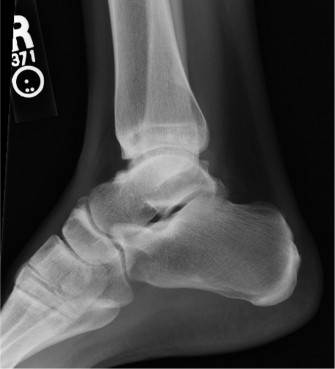

A 32-year-old, professional ballet dancer presents with right ankle pain. She reports that she has had severa…